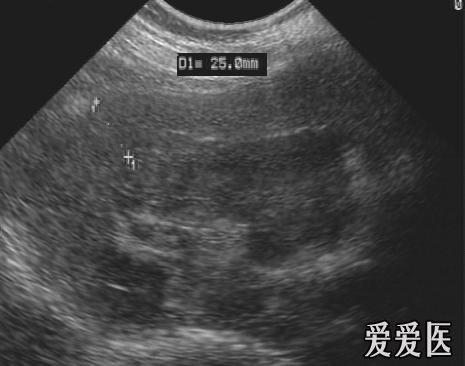

肾挫伤 - 超声医学讨论版 - 爱爱医医学论坛

图片尺寸720x576